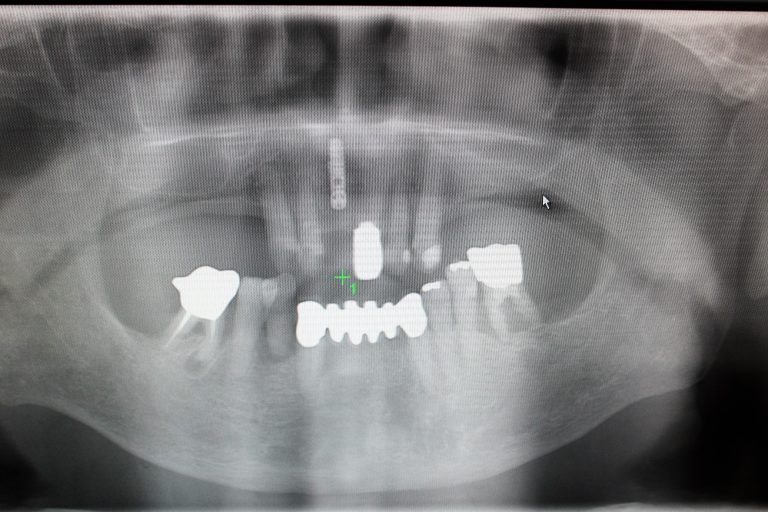

結果は・・・スマートな手術。オペ時間も短くバッチリいい位置にインプラントを

埋入することができました。会心の出来です!

骨質も良く、15mmもの長いインプラントが入りました。このまま1~2カ月

骨に結合するのを待って歯の部分を作っていきます。